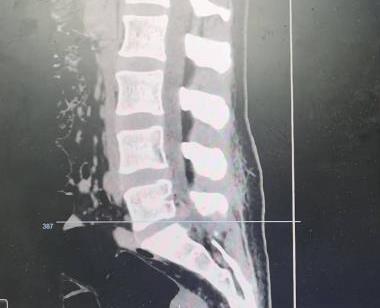

• 单侧双通道内镜下椎间盘切除术治疗钙化型腰椎间盘突出症的临床疗效分析

2025, 31(8):26-31. DOI: 10.12235/E20240693

摘要 (204) HTML (119) PDF 3.09 M (137) 评论 (0) 收藏

摘要:目的 观察单侧双通道内镜(UBE)下椎间盘切除术治疗钙化型腰椎间盘突出症(CLDH)的临床疗效。方法 回顾性分析2020年1月-2022年1月在该院行UBE下腰椎间盘切除术的25例单节段CLDH患者的临床资料。记录手术时间、术后住院时间和术后并发症情况。采用腰腿痛视觉模拟评分法(VAS)评分、腰椎日本骨科协会(JOA)评分和Oswestry功能障碍指数(ODI),评估术前、术后3 d、术后1个月和末次随访的临床疗效。末次随访时,采用改良Macnab标准,评估优良率。结果 术后随访12~24个月,平均(15.60±2.60)个月。手术时间为(58.67±10.73)min,术后住院时间为(4.65±0.63)d。术后3 d、术后1个月和末次随访时的VAS评分和ODI明显低于术前,JOA评分明显高于术前,差异均有统计学意义(P < 0.05)。末次随访时,根据改良的Macnab标准,15例为优,9例为良,1例为可,优良率为96.00%(24/25)。术后并发症:1例神经根腹侧硬膜囊撕裂,长度约5 mm,未行硬膜囊修补术,术后嘱患者卧床5 d,给予补液治疗,患者下床活动未诉头痛等不适,术后MRI显示:未见硬膜外大量积液;1例出现下肢感觉障碍,给予营养神经药物对症治疗,术后1个月随访时恢复。术后影像学检查显示:游离钙化组织基本被完全切除,神经根得到充分减压。末次随访时,未发现复发病例。结论 UBE下腰椎间盘切除术治疗CLDH安全、有效,值得应用于临床。